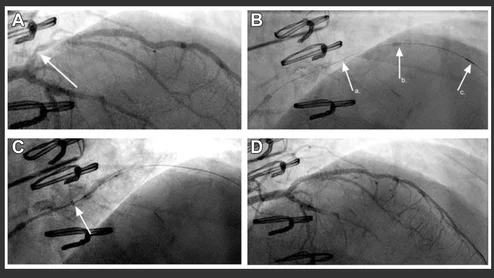

CCTA characterization of a chronic total occlusion with angiographic correlation during percutaneous coronary intervention.

Researchers reviewed dozens of studies to evaluate the long-term value of using CCTA guidance to perform PCI on patients with complete blockages.